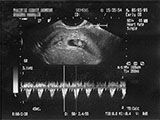

8/3/09. Bottom graph shows heartbeat (already). |